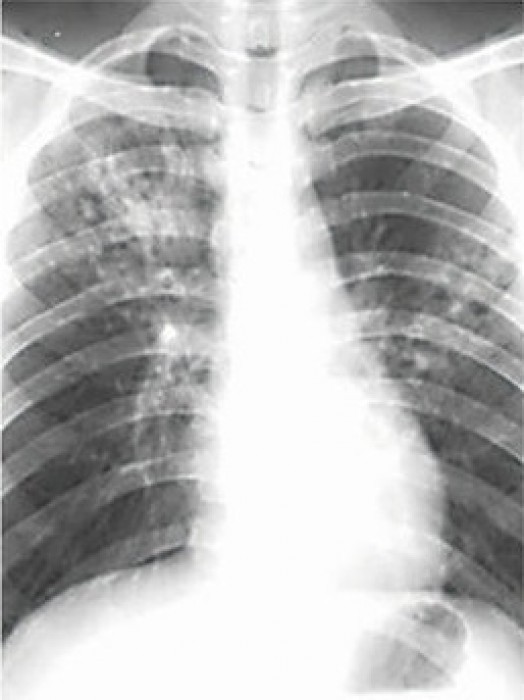

24日、世界結核デーを迎え、専門家は注意を呼び掛けている。結核は、空気感染が多く、肺などの呼吸器官においての発症が目立つ感染症だ。中国は結核患者数が世界で2番目に多い。